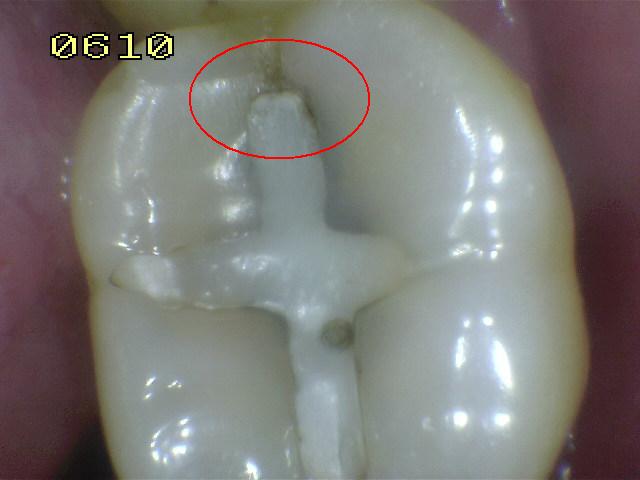

Código 3

(Caries Moderada): Ruptura

localizada del esmalte debido a caries sin dentina visible.

-

Cavidad en el margen de la

restauración/sellante menor a 0,5mm, además de tener una

opacidad o una pigmentación relacionada con

desmineralización que no es compatible con la apariencia

clínica de esmalte sano o con una sombra subyacente en

la dentina.

Utilizar una

sonda con

presión suave. para identificar la pérdida de

anatómica.

Opacidad o decoloración consistente con

desmineralización.